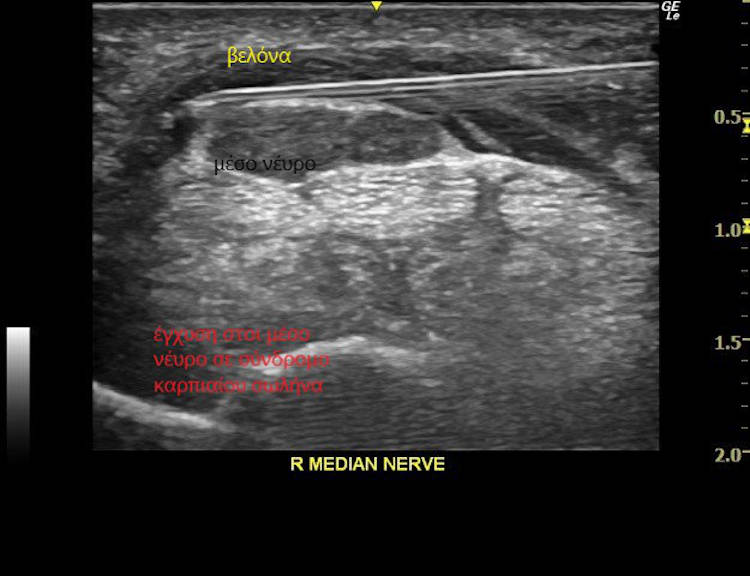

Ο υπερηχοφραφικός έλεγχος διενεργείται με έγχρωμο υπέρηχο τελευταίας γενιάς (ugeo samsung), με τρίπλεξ, ντόπλερ, ελαστογραφία για διάγνωση παθήσεων μυών, συνδέσμων και άλλων μαλακών μορίων όπως παραμορφώσεις της δομής τους (φλεγμονές, κυστικές συλλογές), περιλαμβάνεται ειδικό λογισμικό για καθοδηγούμενες εγχύσεις , ώστε η βελόνα να φτάνει με απόλυτη ακρίβεια στο σημείο στόχευσης,